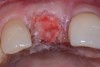

Fig 10. The tooth was extracted; the socket debrided and degranulated; and ridge preservation was performed with FDBA/rhPDGF and an absorbable membrane.

Figure 10

A patient presented with a large periapical lesion, root fracture, and significant loss of buccal bone (Figure 8 and Figure 9). Treatment for this case involved an autogenous bone graft, then implant placement and connective tissue grafting. Recombinant human platelet-derived growth factor-BB was used for ridge preservation and minimally invasive esthetic implant site development with a flapless approach.

The tooth was extracted, and magnification was used while debriding and degranulating the extraction socket. The site was irrigated with a significant amount of sterile water from 10-mL syringes, and the water pressure helped with debridement. Spoon and #4 Gracey curettes were used.

Once degranulated and debrided, the growth factor matrix (eg, freeze-dried bone allograft that was presoaked in rh-PDGF-BB for about 10 minutes) was condensed into the site. The site was then covered with a collagen membrane and sutured.

After healing, the site was evaluated and a high frenum attachment was observed (Figure 10). A frenectomy was performed prior to implant placement, along with a connective tissue graft to thicken the soft tissues.